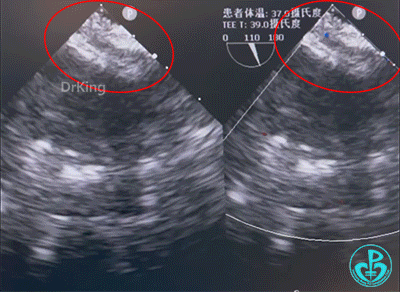

超声影像

超声描述:心脏位置及连接正常。右房右室扩大,左心内径正常。室壁厚度正常,运动正常。左室收缩功能正常范围。房间隔中部可见回声中断,范围约9.0×10.0mm。彩色多普勒显示:房水平左向右分流。室间隔连续完整。各瓣膜形态、结构、启闭运动未见明显异常。彩色多普勒显示:三尖瓣微量反流Vmax 279cm/s,PG 31mmHg,估测肺动脉收缩压36mmHg。大动脉关系及内径正常,左位主动脉弓,弓降部连续。心包腔未见异常。双冠脉起源及近端内径未见明显异常。

超声诊断:

① 继发孔型房间隔缺损(中央型)。

② 彩色多普勒显示:房水平左向右分流。

③ 三尖瓣微量反流。

术中经食道超声复测缺损大小为8.62mm。